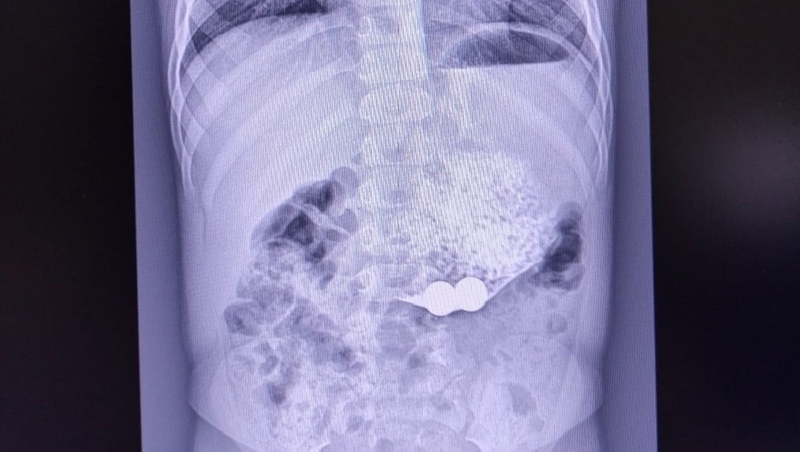

В третьем случае, так как родители не сразу поняли, что произошло, пришлось прибегнуть к операции. Сначала обеспокоенные ставропольцы обратились к врачу по месту жительства с жалобой на многократную рвоту у ребёнка. Снимок показал, что в его тонком кишечнике есть инородные тела. Ими оказались магниты.

«В ходе хирургического вмешательства выявлена кишечная непроходимость, вызванная сращением кишечных петель из-за притягивания магнитов друг к другу»,

Инородные тела удалили, целостность кишки восстановлена. На сегодня маленький пациент продолжает лечение.